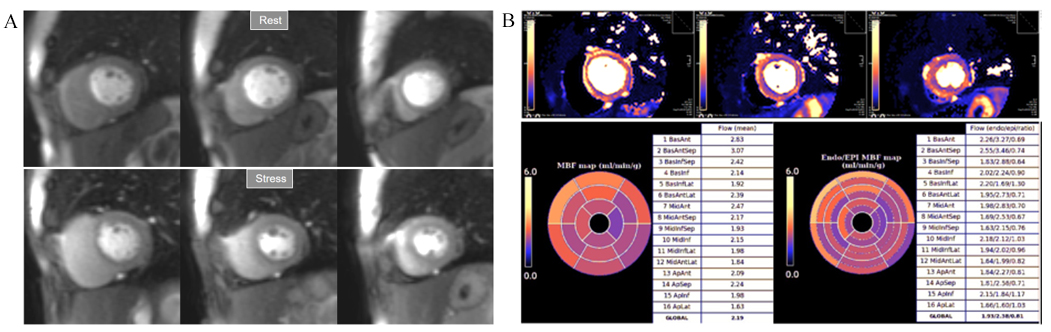

More recently, a new method has been proposed [56] that includes several important solutions contributing to a reliable implementation on the routine workflow of a CMR exam [57]. Firstly, it is based on a dual imaging sequence strategy (Fig. 24), where low-resolution blood pool images used for estimation of the AIF are followed by multi-slice 2D high-resolution myocardial perfusion sequence. The total duration of the scheme is around 500 msec, that allows for the obtention of 3 slices sampled every heart cycle, as long as the heart rate is below 120 b.p.m. AIF extraction from the low-resolution sequence has proven to be reliably obtained automatically [58] (Fig. 25). Second, motion and surface coil intensity correction are applied to both AIF and perfusion images [57, 59]. Third, a process of SI conversion into gadolinium concentration [Gd] units is performed for both sequences [56] (Fig. 26). Fourth, and most important, AIF [Gd] curve and perfusion [Gd] images are inputted into flow mapping step for pixel-wise myocardial flow mapping [57] rendering quantitative values of MBF (in mL/min/g) (Fig. 27). Based on a process of deep learning [60], myocardial segmentation and allocation of flow values are automatically processed (Fig. 28) and integrated into the MRI scanner using the Gadgetron streaming reconstruction software [61, 62]. The final output of the process consists on a bull’s-eye plot of color-encoded MBF values on the LV 16-segment model, and the listed numerical values of absolute flow at stress and at rest and, also, the derived MPR, each of them calculated for the endo- and epicardial halves of the segment (Fig. 29). The presence of inducible perfusion defects is thus detected not only visually on the perfusion color map, but also quantitatively estimated by the absolute values of stress MBF and the corresponding MPR of the involved myocardial segments (Fig. 30). Of note, in case of a suboptimal effect of the vasodilator agent, a lack of increase in stress MFB and MPR values is observed, leading to a potentially false positive diagnosis, in contrast with the visual assessment of perfusion, which, in this case, as stated above, would not show induced defects, with the potential for a false negative.

Fig. 29.Bull’s-eye plot segmented values of MBF. Shown are both, global (left panels) and distributed for endo- and epicardial regions (right panels) at stress (A) and at rest (B). Also, data on the resultant MPR values are presented with the same format (C).

Fig. 30.QP study in a patient with an inducible defect. A defect at the inferior basal region is detected in the conventional stress perfusion sequence (white arrow). QP maps from the corresponding basal segments show transmural intense reduction of the stress MBF and MPR at the inferior segment (red arrow and asterisks), with less severe involvement of the infero-lateral one (blue arrow and asterisks). Observe the reduced stress MBF in comparison with the rest value of the inferior segment, with a resultant MPR value significantly decreased, inverted actually (0.93), indicating coronary steal phenomenon and, in accordance, probably severe inducible ischemia of the region.